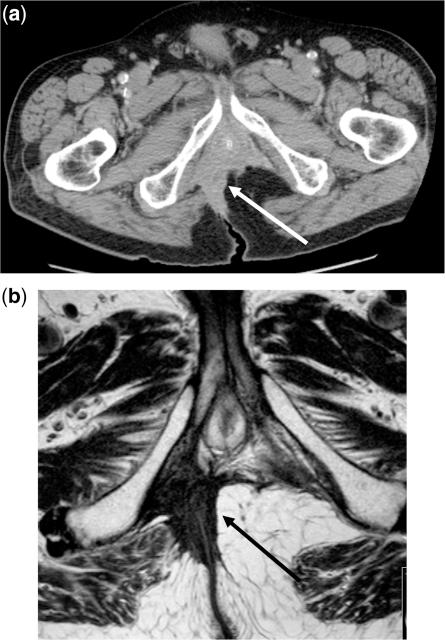

Radical resection is the only potential cure for patients with locally advanced primary and recurrent rectal cancer and is considered curative only when the histologic margins are clear of tumour. Early diagnosis of the disease is essential as it increases the likelihood of a potentially curative resection and prevention of dissemination. Clinical examination, tumour markers and radiologic modalities such as ultrasonography, computed tomography, magnetic resonance imaging and positron emission tomography are routinely used in an effort to accurately stage these patients and provide useful information for the selection of patients for further treatment/management. This review describes the methods of staging patients with locally advanced primary and recurrent rectal cancer prior to surgery emphasizing the role that radiologists have in this process.

根治性切除术是局部晚期原发性和复发性直肠癌患者的唯一潜在治愈方法,只有当组织学切缘无肿瘤时才被认为是治愈性的。早期诊断疾病至关重要,因为这增加了潜在治愈性切除的可能性,并防止了疾病的扩散。临床检查、肿瘤标志物和影像学方式,如超声、计算机断层扫描、磁共振成像和正电子发射断层扫描,通常用于准确分期这些患者,并为进一步治疗/管理的患者选择提供有用的信息。本综述描述了在手术前对局部晚期原发性和复发性直肠癌患者进行分期的方法,强调了放射科医生在这一过程中的作用。